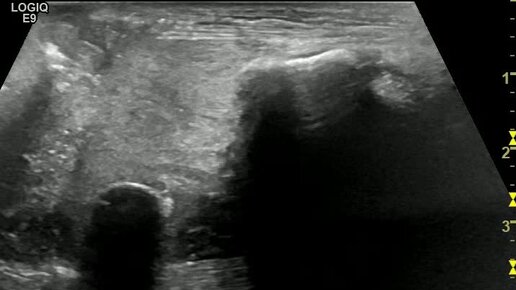

Резиновая пуля в мягких тканях кисти

Ультразвуковые находки от врача УЗД Зорина Я.П.